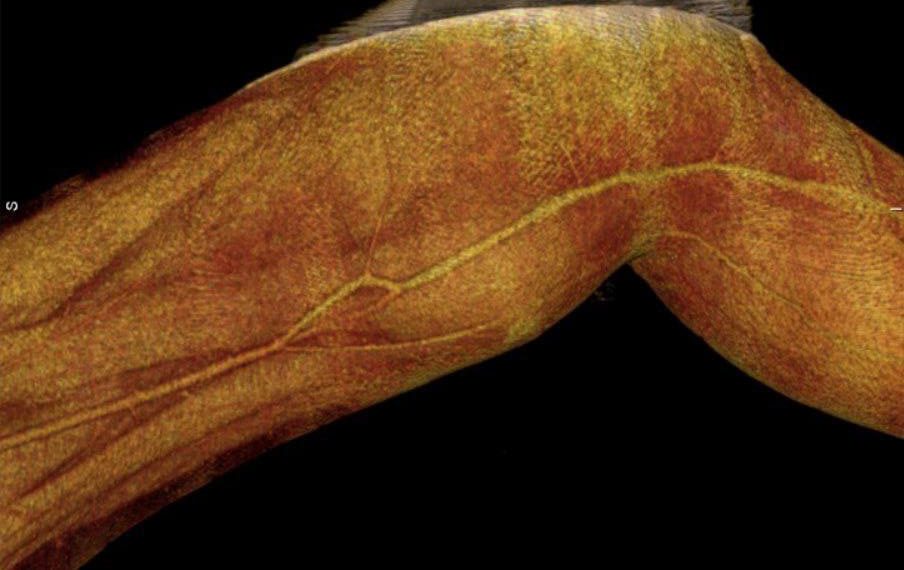

Врачи вскрыли и удалили гематому, извлекли осколок, затем провели протезирование поверхности бедренной артерии.

«То есть, мы взяли участок большой подкожной вены и заменили им четыре сантиметра бедренной артерии. Если бы операция не была выполнена вовремя, мог произойти разрыв гематомы или тромбоз периферического русла, в этом случае потребовалось бы проведение ампутации», — рассказал и.о. заведующего отделением торакальной хирургии Ульяновской областной клинической больницы Сергей Мустафин (на фото).